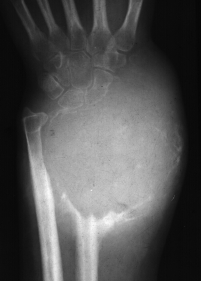

▌膨胀性破坏

膨胀性破坏是地图样破坏的特殊形式,影像学表现为骨质破坏区骨膨胀,周围可见不同程度扩张的骨壳(图 5、图 6、图 7、图 8)。膨胀性破坏是由于肿瘤从骨皮质内面破坏,骨外膜增生形成新生骨造成膨胀的。引起膨胀性破坏见于大多数良性肿瘤和肿瘤样病变如单纯性骨囊肿,动脉瘤样骨囊肿、内生软骨瘤和软骨粘液纤维瘤等,少数也可见于恶性肿瘤如转移瘤、骨髓瘤等。

图 7.膨胀性破坏:内生软骨瘤